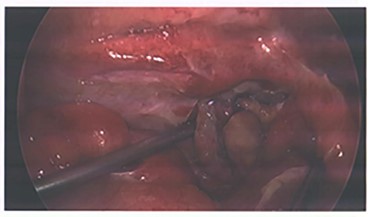

At angiogram, the superior mesenteric artery (SMA) was successfully cannulated, and the patient was found to have active extravasation from the appendiceal artery (Fig. 2). This was successfully controlled with a 3 mm coil.

Images from angiography. (A) Pre-embolization, demonstrates appendiceal lumen filled with contrast. (B) Demonstrated coiled artery.